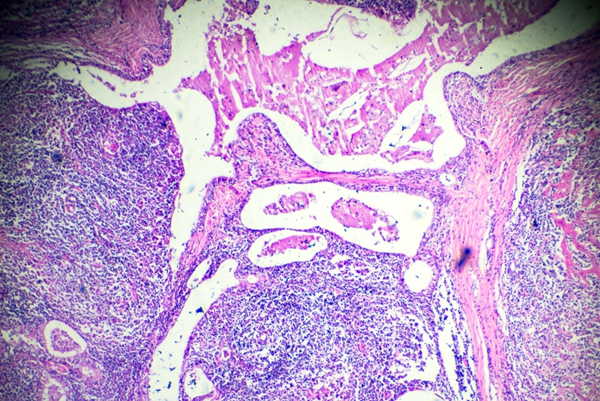

暗视野显微镜检查:适用于早期梅毒,可直接观察皮损渗出液或淋巴结穿刺液中的梅毒螺旋体,是一种直观的检查方法。